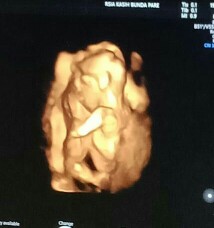

janin telungkup saat USG

Bagi pengalaman dong, Babyku posisi begini pas DiUSG usia kehamilan 17w. Gkpapa kan bund? Soalnya dokter pas buru2 mau operasi waktu itu, jd ndak sempat menjelaskan